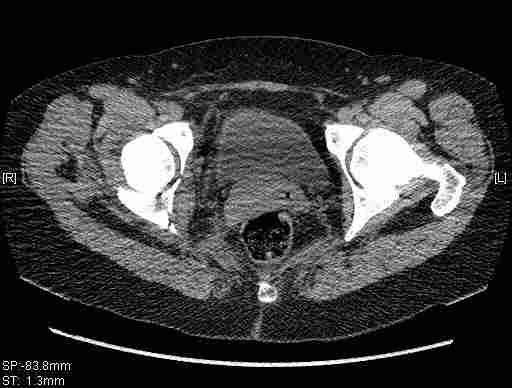

Удалось сегодня вывести пациентку в соседнюю больницу, где есть кт. Срезы сделаны только горизонтальные.